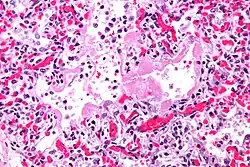

| Micrograph showing hyaline membranes, the key histologic feature of diffuse alveolar damage. H&E stain. | |

- The edema contributes to the deposition of a hyaline membrane (composed of dead cells, surfactant, and proteins) along the alveolar walls. Hyaline membranes are characteristic of DAD.

In order to make a diagnosis of DAD a biopsy of the lung must be obtained, processed, and examined microscopically. As described above, the hallmark of diagnosing DAD is the presence of hyaline membranes.[1] Most frequently DAD is associated with ARDS, but since there are clinical criteria (see Berlin criteria above) upon which we can diagnose ARDS, it is often unnecessary in all cases to obtain invasive biopsies of the lung. Additionally, there are limitations of the biopsy test since it is possible to sample a potentially normal area of lung even though there is DAD in the rest of the lung, resulting in a false negative.[1]